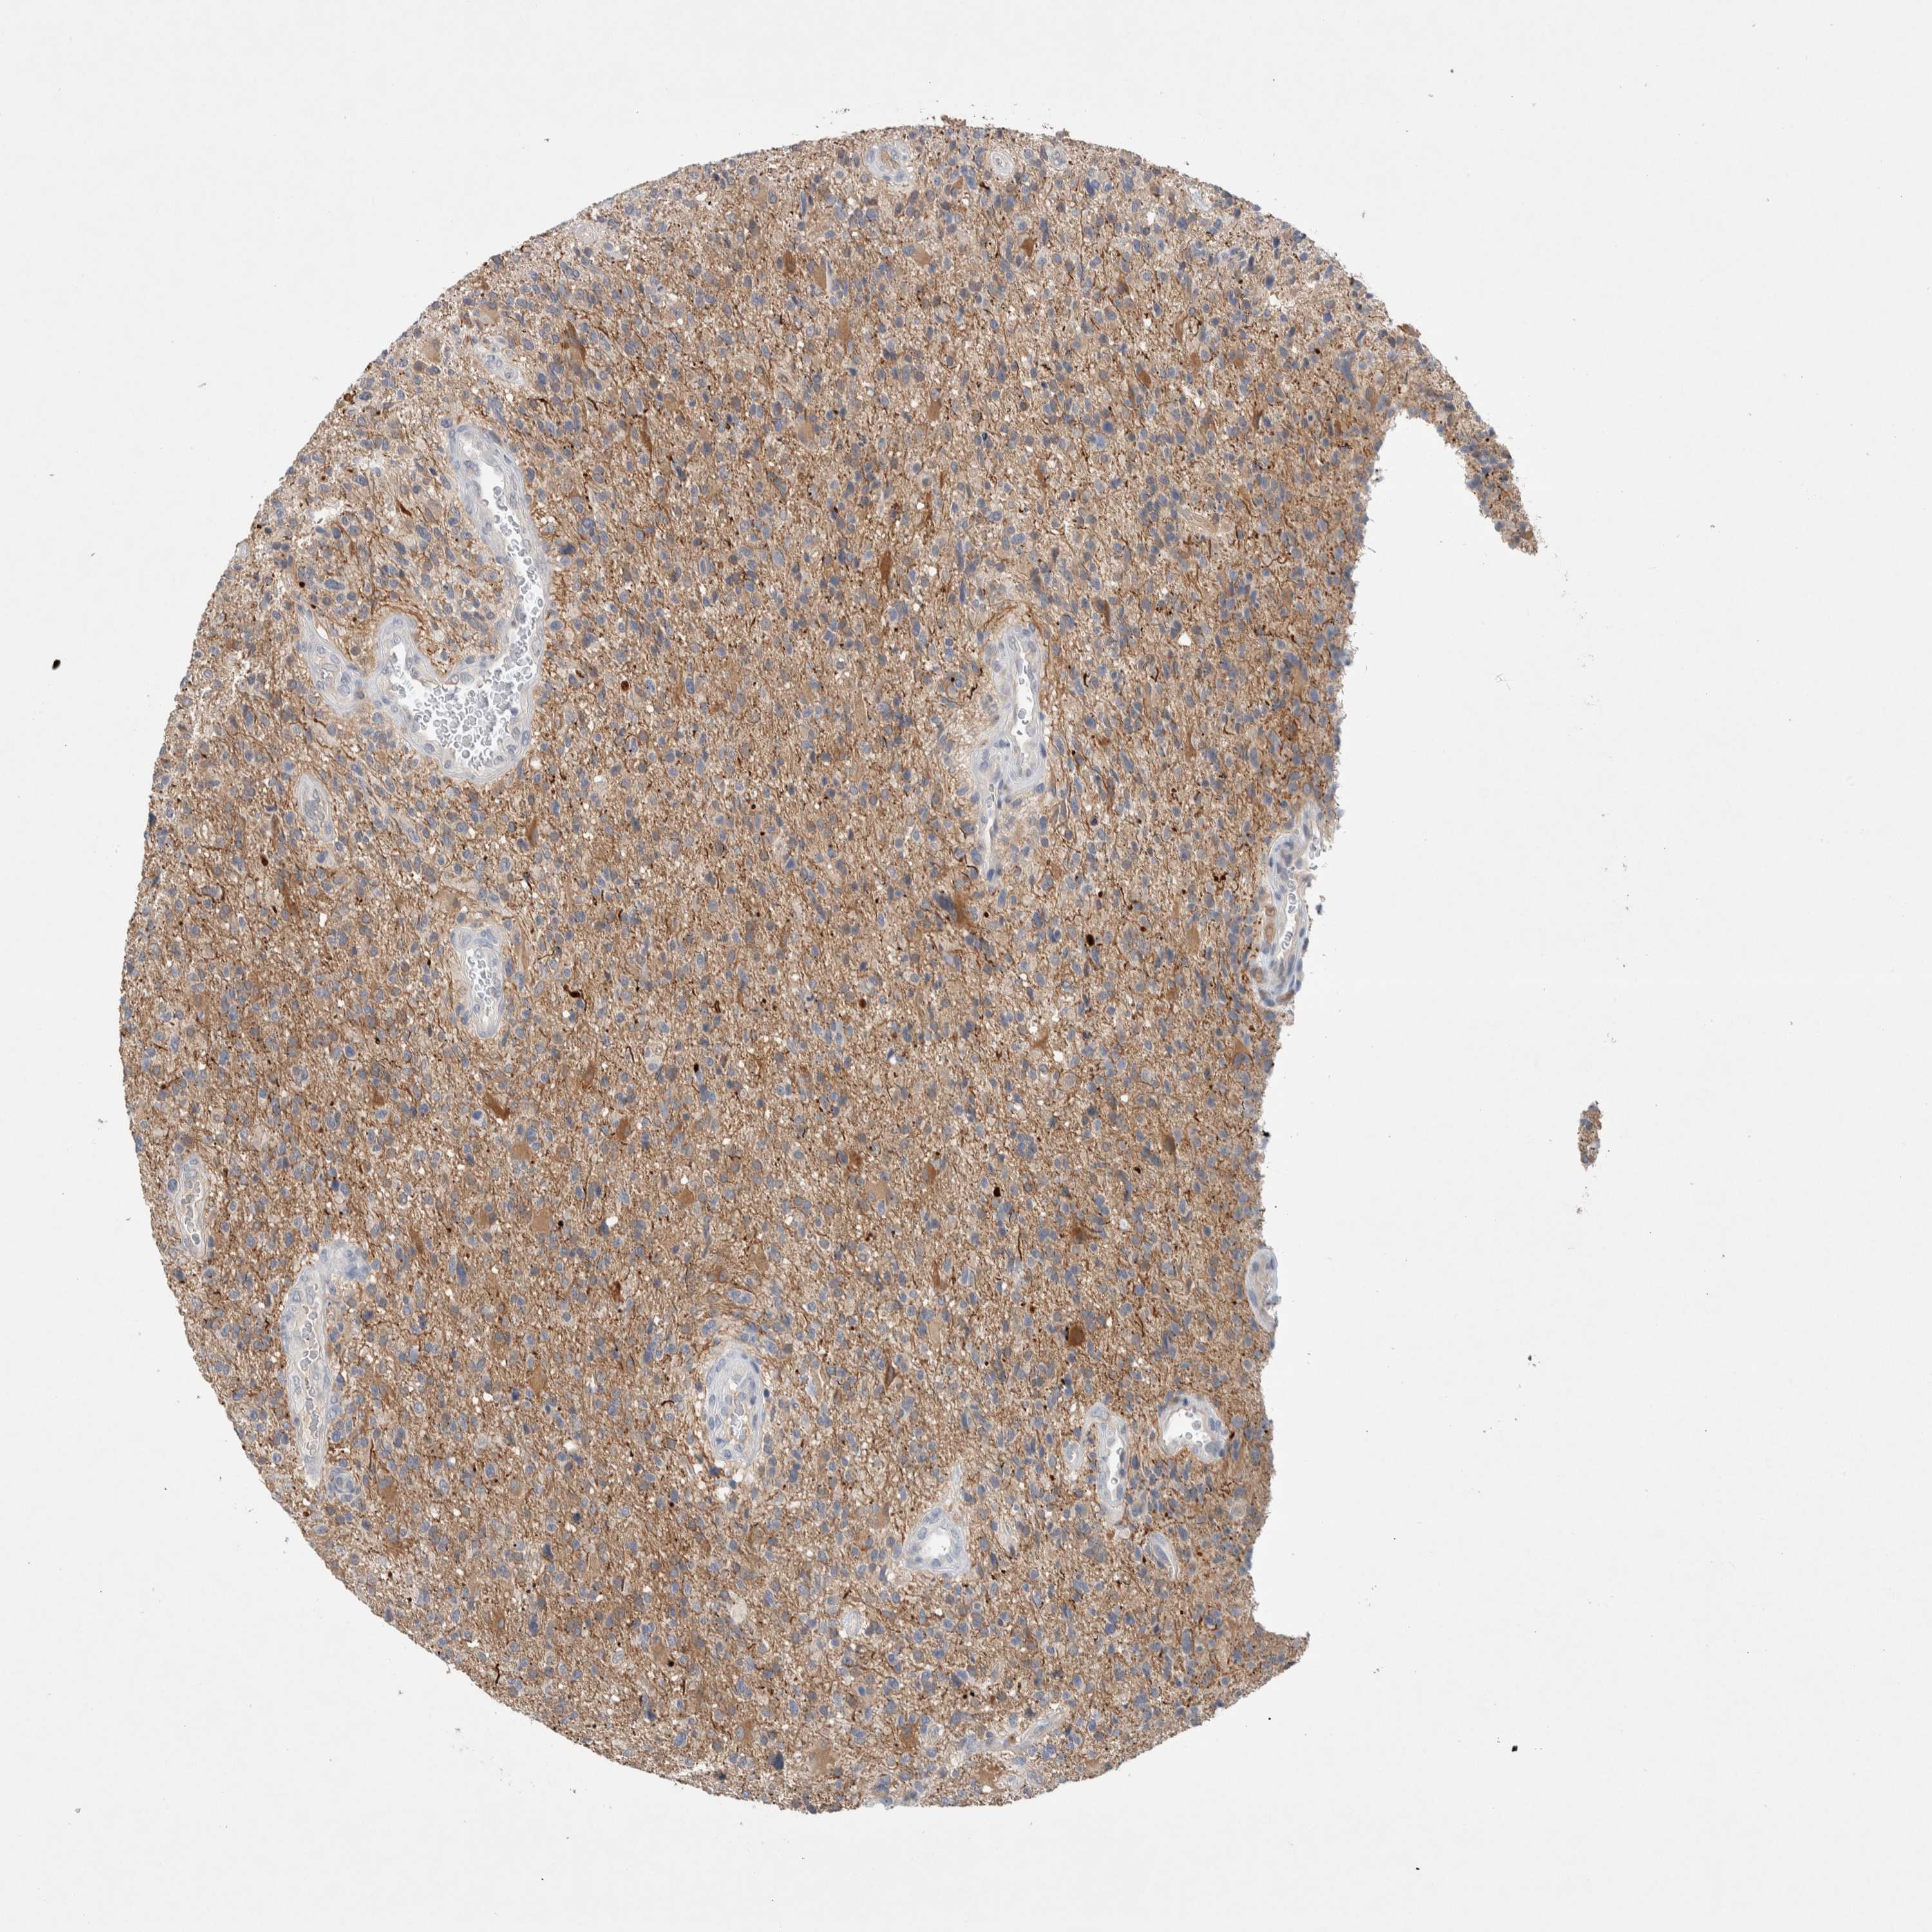

GLIOMA - Protein expressioni

A mouse-over function shows sample information and annotation data. Click on an image to view it in a full screen mode. Samples can be filtered based on level of antibody staining by selecting one or several of the following categories: high, medium, low and not detected. The assay and annotation is described here.

Note that samples used for immunohistochemistry by the Human Protein Atlas do not correspond to samples in the TCGA dataset.

Antibody stainingi

Antibody staining in the annotated cell types in the current human tissue is reported as not detected, low, medium, or high, based on conventional immunohistochemistry profiling in selected tissues. This score is based on the combination of the staining intensity and fraction of stained cells.

Each image is clickable and will lead to virtual microscopy that enables deeper exploration of all samples and also displays staining intensity scores, fraction scores and subcellular localization as well as patient and tissue information for each sample.

Antibody HPA023938

Antibody HPA023945

Antibody HPA024011

Antibody CAB020841

Staining

High

Medium

Low

Not detected

Intensity

Strong

Moderate

Weak

Negative

Quantity

>75%

75%-25%

<25%

None

Location

Nuclear

Cytoplasmic/membranous

Cytoplasmic/membranous,nuclear

Glioma, malignant, High grade

Glioma, malignant, Low grade